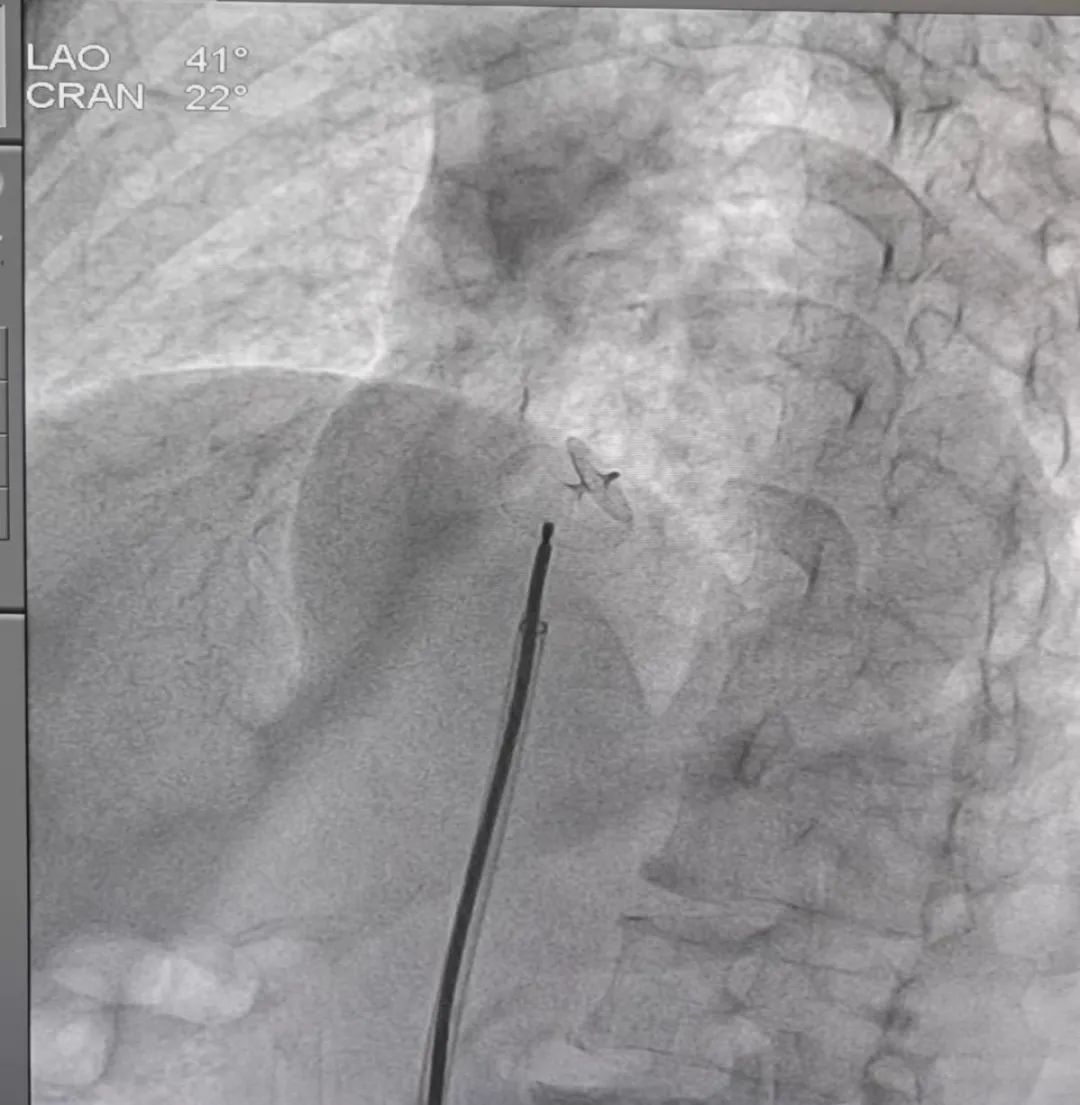

据悉,患者罗女士(化名)来自拉萨市,今年61岁,既往有反复头晕、心慌等不适症状,7月6日到我院心血管内科就诊。经右心造影检查明确患者为卵圆孔未闭,经心血管内科全科室研究讨论后,决定为该患者进行卵圆孔未闭介入封堵术。13日下午,在心内科 主任 朱永彪的指导下,我院心血管内科通力合作,用介入封堵术取代外科手术,通过一根导管,经右股静脉途径将封堵器沿输送鞘置入并成功封堵卵圆孔,术中多角度显示封堵器形态良好。

▲手术成功